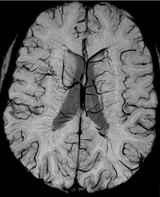

SWIp image. Ingenia 3.0T.

Exquisite depiction of venous brain structures